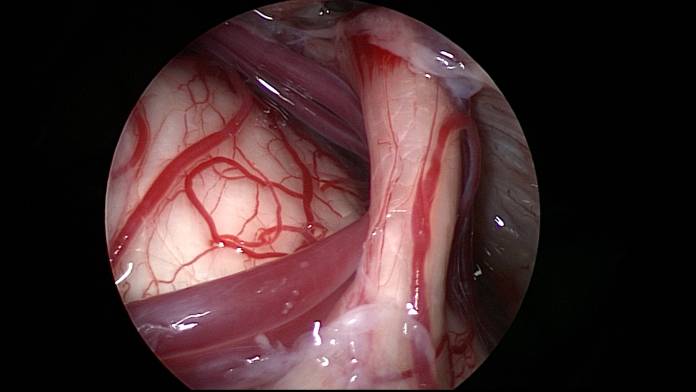

Prof. Schroeder: Die operative Therapie der Trigeminusneuralgie ist sicher schon optimal entwickelt, sodass hier keine weiteren größeren neuen Erkenntnisse zu erwarten sind. Die mikroskopische und auch endoskopisch assistierte Inspektion der Trigeminuswurzel erlaubt die Untersuchung des gesamten Trigeminusnerven vom Hirnstamm bis zum Eintritt in die Schädelbasis, sodass man hier mögliche Irritationen sehr gut erkennen kann. Geforscht wird vor allem an neuen Medikamenten zur Behandlung der Trigeminusneuralgie. Gegenwärtig wird die Botulinumtoxin-Injektion in größeren Studien geprüft.